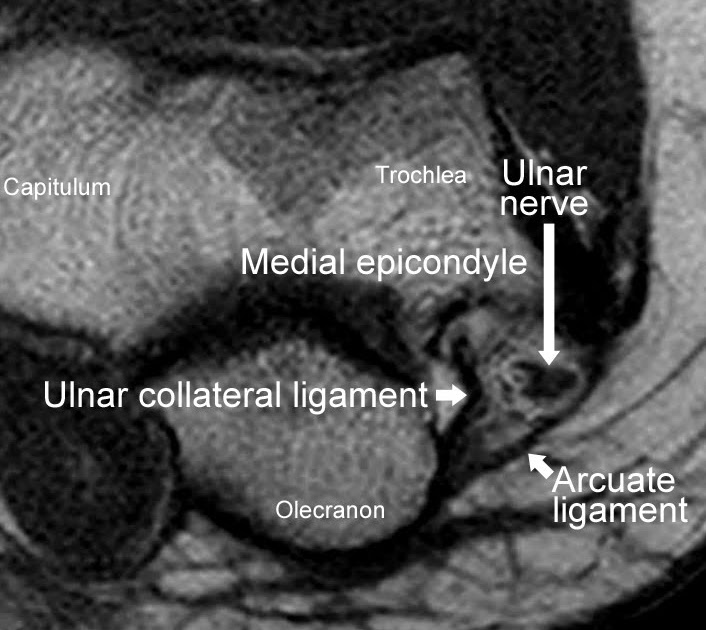

Cubital Tunnel View X Ray Positioning . Cubital tunnel syndrome (cuts) is the second most common peripheral mononeuropathy in the upper extremity, 1 with an estimated. The cubital tunnel is a space through which the ulnar nerve passes posterior to the medial epicondyle of the humerus. Cubital tunnel syndrome (cuts) is the compression of the ulnar nerve as it courses through the cubital tunnel near the elbow at the.